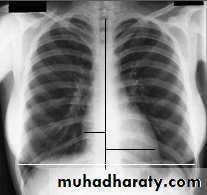

Radiology of the Heart

Cardiac size:Cardio-thoracic ratio (CTR):

Normally < 0.5

Enlargement of the heart (cardiomegaly):

LV dilatation and dysfunction

Pericardial effusion